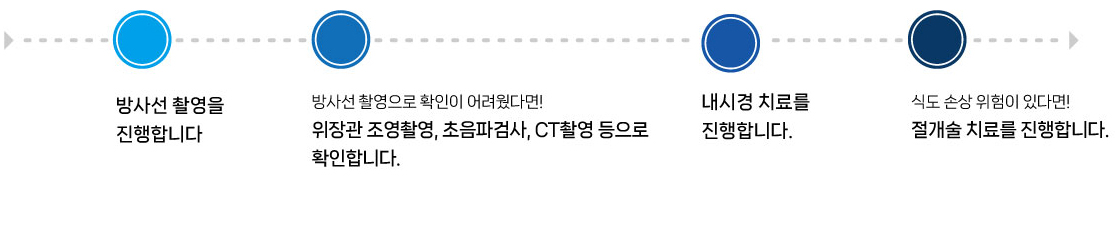

SNC 내시경 치료 진행과정

자두씨 이물 섭취

치료 후 (자두씨 제거 모습)

방사선 검사 (철사 이물 확인)

위 내시경 치료 모습